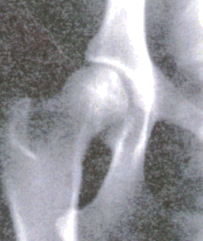

Fyrstu einkenni mjaðmaloss sem sjást á röntgenmynd er að augnkarlinn grynnist og lærleggshöfuð verður flatara. Alvarlegast er mjaðmalosið þegar augnkarlinn er nánast horfinn og afmyndað lærleggshöfuðið liggur utan augnkarlsins.

Röntgenmynd er dæmd eftir ástandi mjaðmaliðarins sem fær einkunn frá A-E. (Samkvæmt stöðlum FCI, Bretar hafa t.d. annað kerfi við mat á röntgenmyndum.) Þegar lærleggshöfuð og augnkarl passa fullkomnlega saman, fær liðurinn einkunnina A, en E þegar lærleggshöfuðið er nánast utan augnkarlsins.